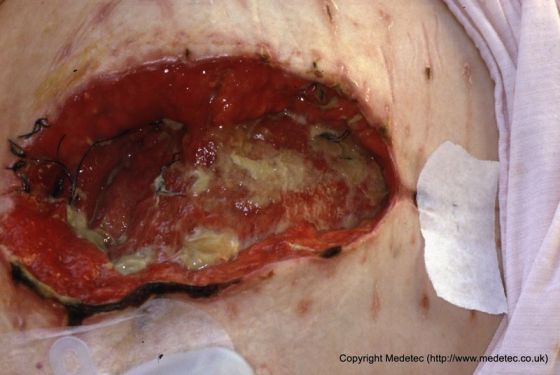

Partial dehiscence of a surgical wound will present as superficial layers or a small amount of tissue layers being reopened. Complete dehiscence, however, will present as all layers being separated with underlying tissue and organs being exposed and sometimes protruding through the wound opening. Other symptoms of dehiscence include visibly broken sutures before the wound has healed completely, as well as renewed pain, bleeding and drainage from the surgical wound site.

Image Source: Medetec (www.medetec.co.uk). Used with permission.